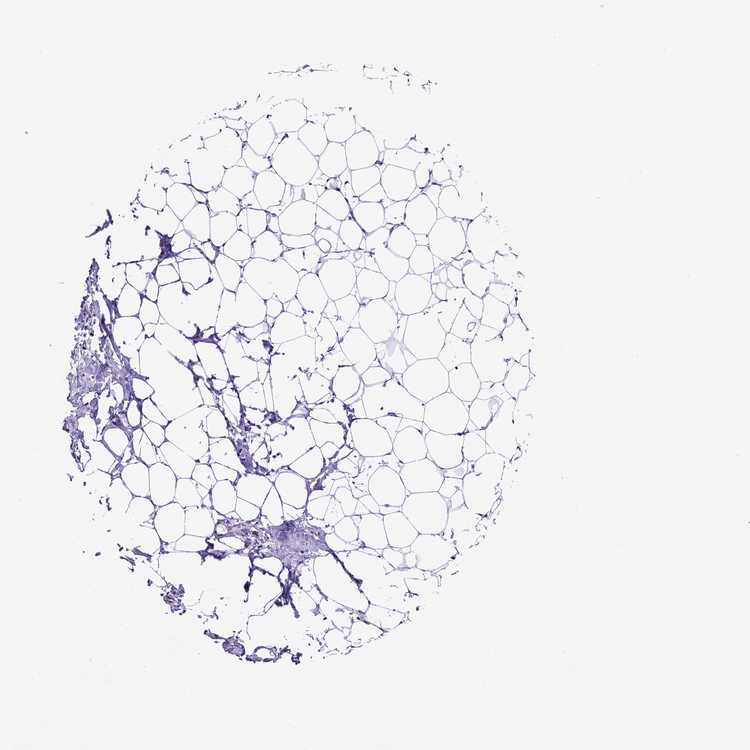

BREAST - Antibody stainingi

Antibody staining in the annotated cell types in the current human tissue is reported as not detected, low, medium, or high, based on conventional immunohistochemistry profiling in selected tissues. This score is based on the combination of the staining intensity and fraction of stained cells.

Each image is clickable and will lead to virtual microscopy that enables deeper exploration of all samples and also displays staining intensity scores, fraction scores and subcellular localization as well as patient and tissue information for each sample.

Antibody HPA053793

Adipocytes Not detected

Glandular cells Not detected

Myoepithelial cells Not detected